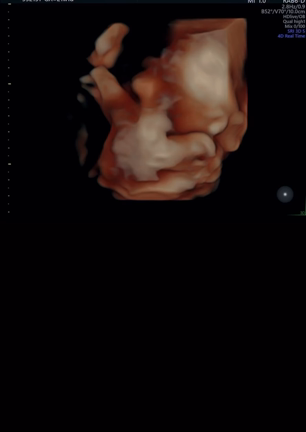

胎児超音波検査してみた【動画あり】